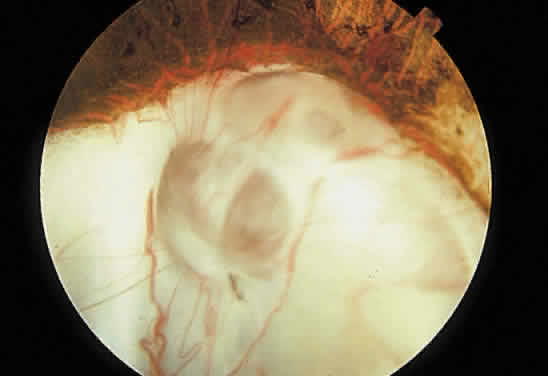

Retinochoroidal colobomas are glistening white or yellow defects with distinct borders that occur inferior or inferonasal to the optic disc (Fig. 12). They may extend up to and involve the optic disc (Fig. 13), or they may be seen as isolated chorioretinal defects. The margins of the coloboma often are pigmented, and the defect is filled with abnormal retinal tissue. Anteriorly, the defect can extend as far as the iris and produce an inferonasal gap (Fig. 14). These anomalies may occur in otherwise normal persons or in association with chromosomal abnormalities or multisystem diseases, such as trisomy 13, the Aicardi syndrome, Goldenhar's syndrome, and the CHARGE association.148,152,153 Occasionally, autosomal dominant or recessive inheritance patterns are found, but often none are evident.152 In families with autosomal dominant inheritance, variable expression of the genetic trait makes genetic counseling difficult.154

Fig. 13. Retinochoroidal coloboma involving the optic disc and inferonasal fundus. The borders of the abnormality are nonpigmented, and the defect appears to be filled with fibroglial tissue.

Embryologically, retinochoroidal colobomas arise from failure of the embryonic fissure to close. Consequently, the inner and outer layers of the optic cup are abnormal in this region. The inner layer (sensory retina) usually is present as a membrane of undifferentiated retina that may have blood vessels going through it (see Figs. 12 and 13). The outer layer (RPE) is absent, and since the choroid is dependent on the RPE for its development, it also is lacking.